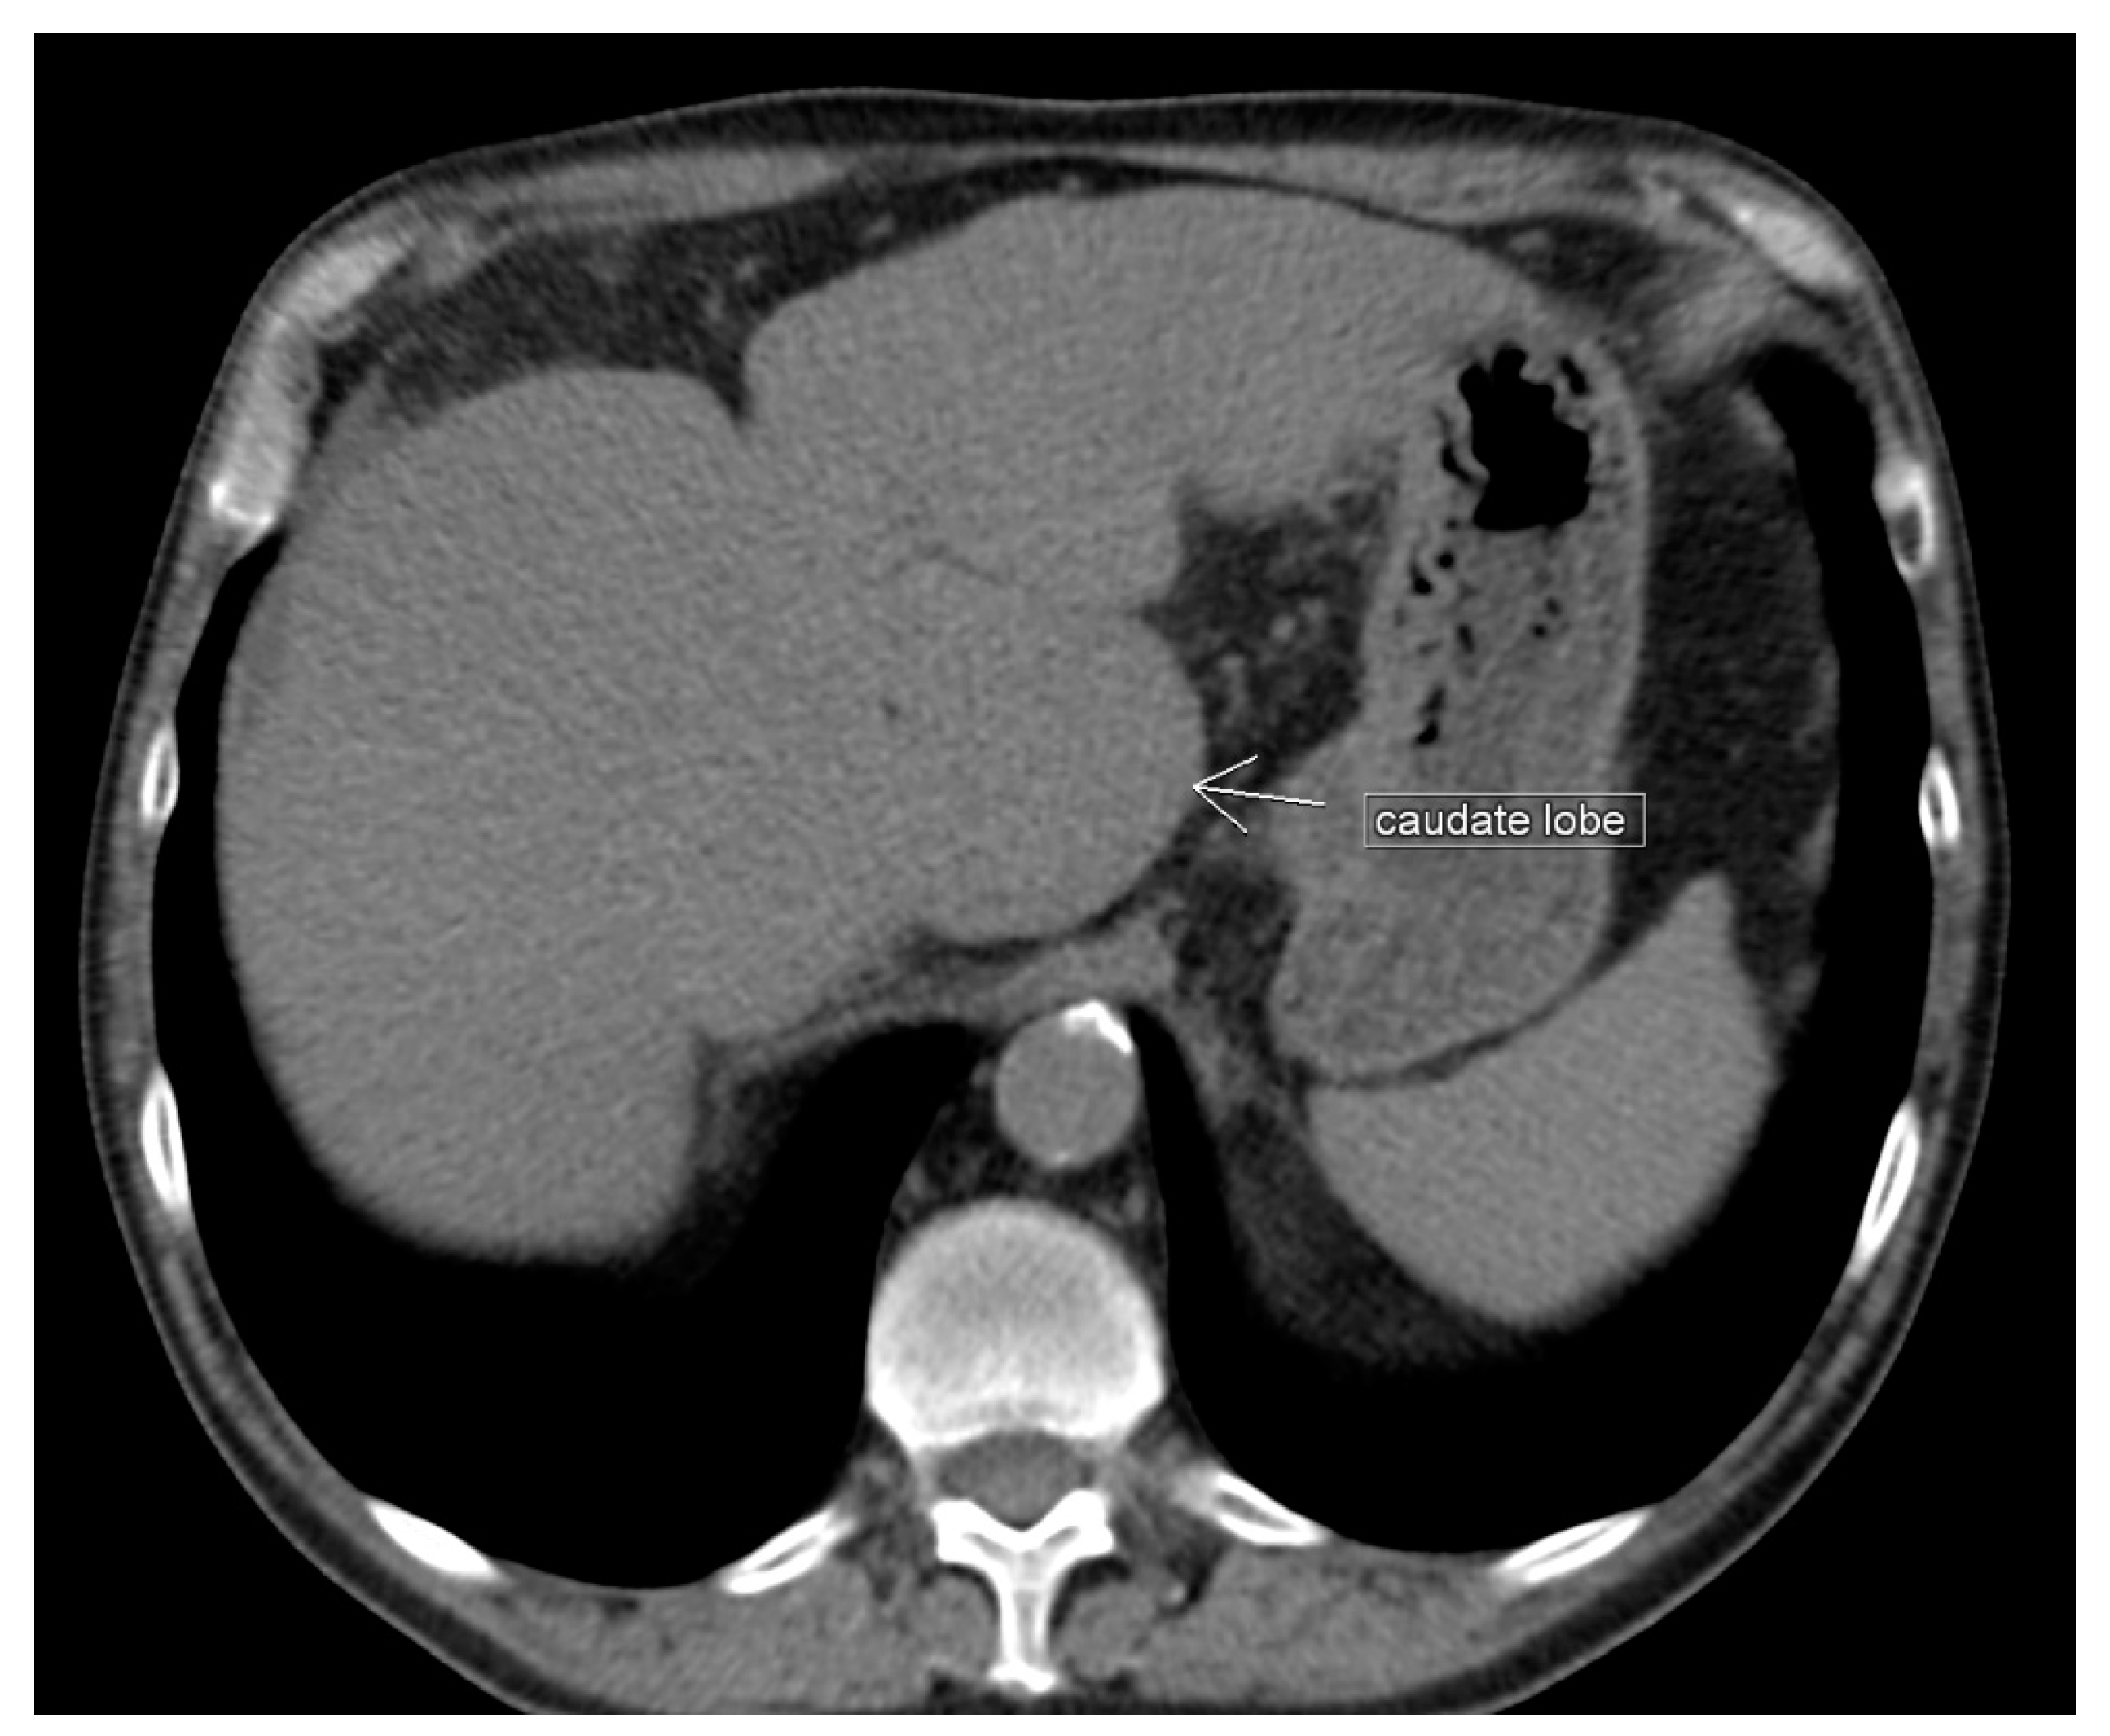

3.4. Papillary Process (Spiegel’s Lobe) and Caudate Process of the Caudate Lobe

Significance of the Papillary Process (Spiegel’s Lobe) and Caudate Process of the Caudate Lobe of the Liver in Ovarian-Cancer Surgery